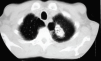

Fig. 2. Tomografía computarizada torácica con lesión cavitada en LSI.